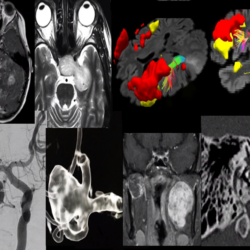

Curso Integrador de Neurorradiología